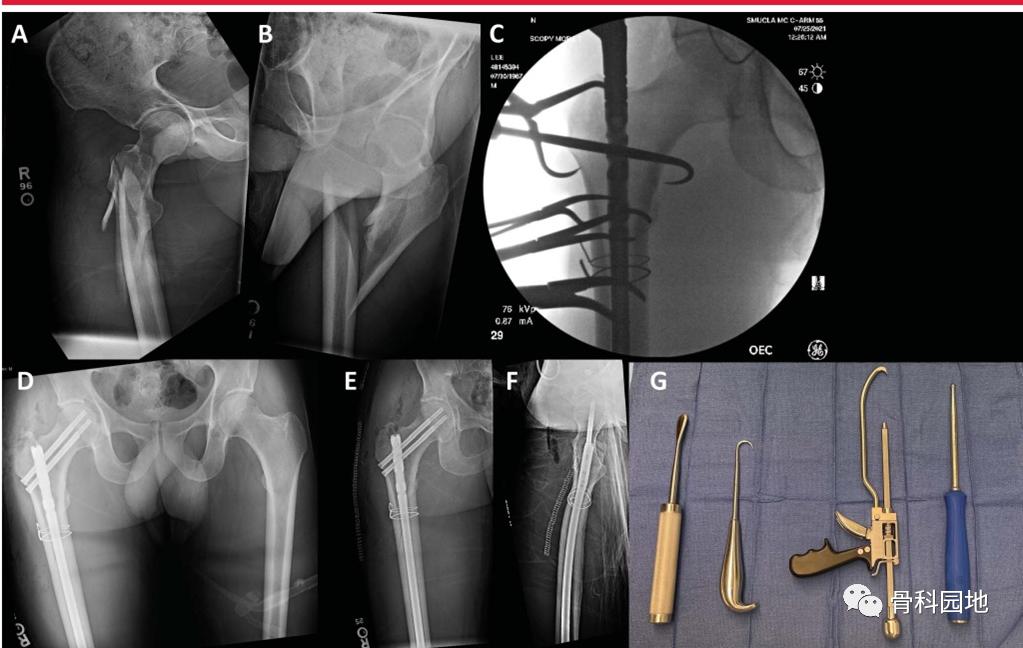

七、在需要时,使用辅助复位工具

多种辅助技术和工具可用于骨折复位,包括尖头复位钳、环扎钢丝、骨钩、球钉推杆、共线钳和单皮质钢板(下图。

A和B,损伤AP和右侧髋侧位x线片显示髋粗隆粉碎骨折。C,透视图像显示用于复位的多点复位钳和环扎钢丝。D, AP骨盆术后显示股骨转子周围骨折复位良好。E, AP术后图像显示骨折复位良好,重建钉置入。F,侧位图像显示髋关节转子周围骨折位置良好,复位良好。G,显示辅助经皮复位工具,包括(从R到L) Cobb,骨钩,共线钳和球钉推杆。